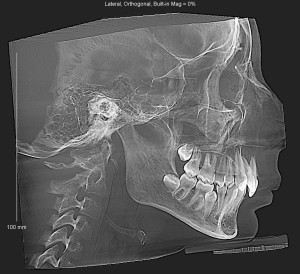

У дочери узкая челюсть. Боковые резцы на верхней челюсти травмоопасно расположены вперед. На нижней челюсти заложена одна пятерка, находится в горизонтальном положении. С другой стороны пятерки нет. Врач предлагает удалить нижнюю пятерку, обе верхних и 4 зуба мудрости (тоже заложены, не вышли). И ставить брекеты.

Здравствуйте. По снимкам видна скученность и узкая челюсть, поэтому для выравнивания зубных рядов действительно иногда приходится выбирать между удалением премоляров или более сложной схемой с вытяжением ретинированных зубов.

Вот есть еще такие снимки

По этим снимкам также видно выраженную скученность зубов и анатомически узкие зубные дуги. Нижняя пятёрка лежит неправильно, а верхним зубам явно не хватает места. Это подтверждает, что вариант с удалением части премоляров более предсказуем и стабильный для получения симметрии и правильного прикуса.